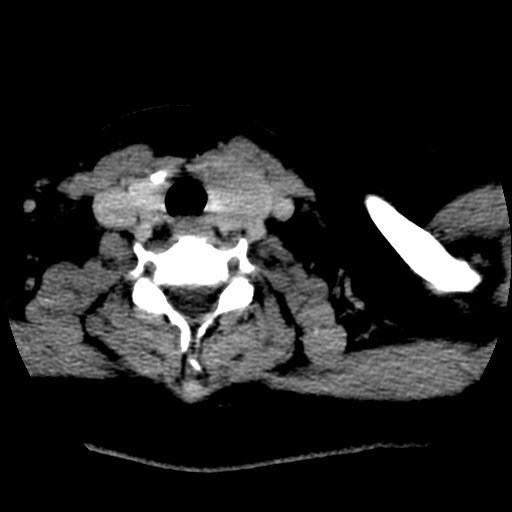

标题: CT25491:女,55岁,发现左侧甲状腺肿块一个月。 [打印本页]

女,55岁,发现左侧甲状腺肿块一个月,彩超示:甲状腺多发结节伴左叶结节液化。

左右叶都有,峡部也受累,有钙化,考虑结甲可能性大。

考虑右叶结节性甲状腺肿,伴左叶钙化。主要(1)密度均匀,边境清。(2)病灶与血管界限清。